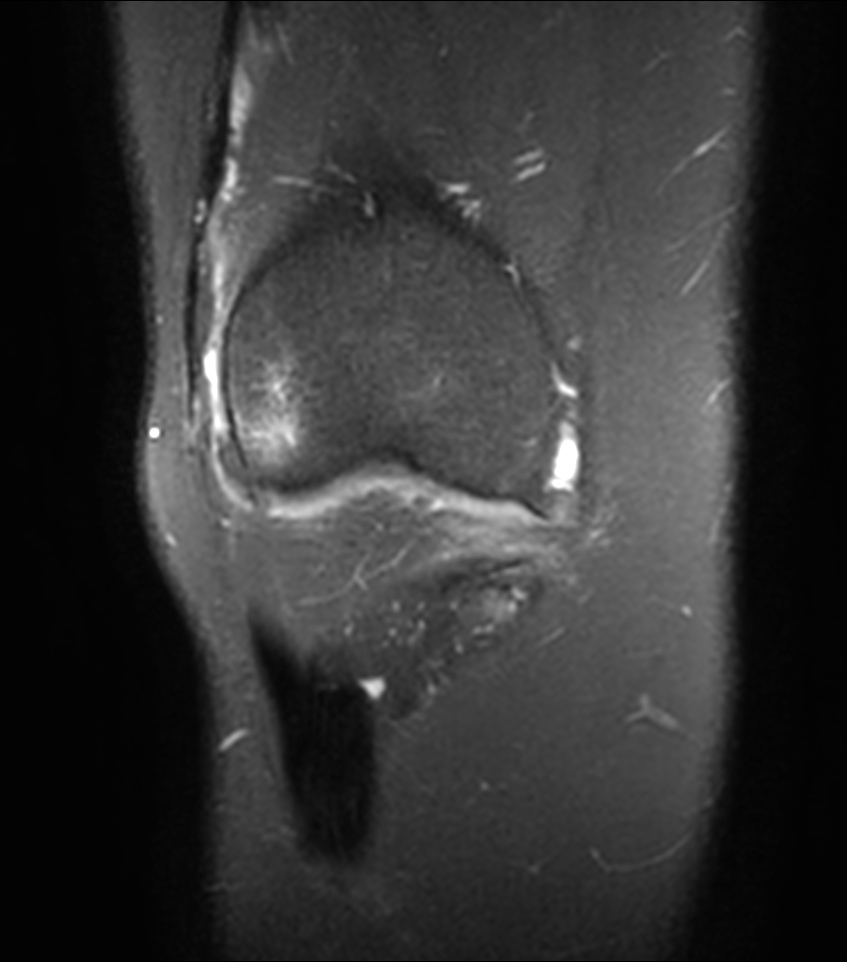

Coronal T1w TSE